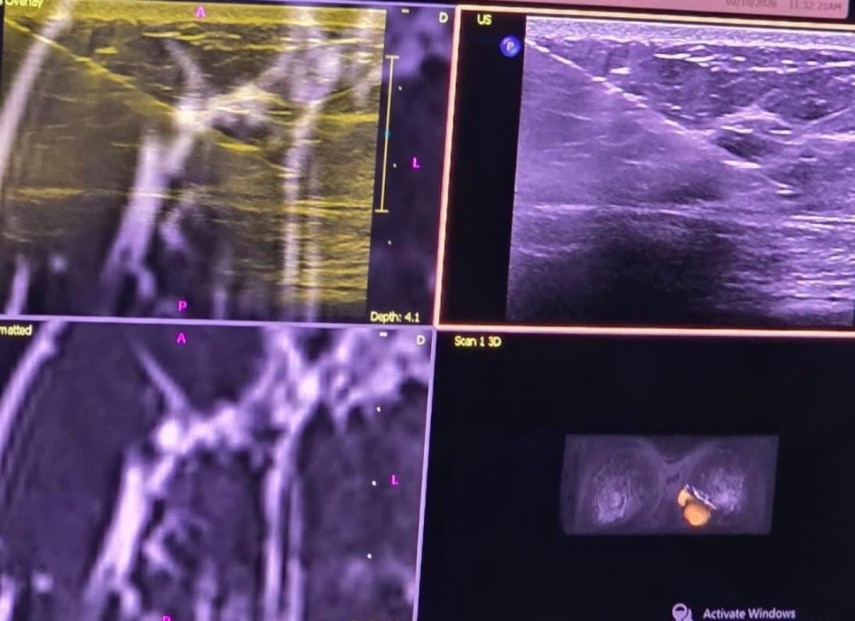

Spitalul Clinic Județean de Urgență (SCJU) Constanța marchează un moment important pentru medicina românească, realizând în premieră națională prima puncție mamară ecoghidată utilizând tehnologia de fuziune a imaginilor IRM.

În urma investigației s-a descoperit o leziune suspectă la nivelul sânului drept însă, densitatea crescută a țesutului mamar a impus completarea investigațiilor cu un examen IRM, înainte de prelevarea biopsiei. Aici a apărut elementul surpriză: a doua leziune suspectă, la nivelul celuilalt sân. In consecință, s-a decis biopsierea ambelor formațiuni.

Prima leziune a putut fi abordată fără dificultăți sub ghidaj ecografic, însă cea de-a doua a impus o tehnică avansată – corelarea imaginilor IRM cu ecografia în timp real – pentru o localizare precisă și o biopsiere sigură.

“Biopsia sub ghidaj IRM rămâne standardul de aur pentru leziunile detectabile exclusiv prin această metodă, dar tehnica de fuziune imagistică oferă o soluție valoroasă în cazurile dificile și crește precizia diagnosticului”, a declarat dr. Alexandru Gavrilă, medic radiolog, specialist în mamografie.

Spitalul Clinic Județean de Urgență „Sf. Apostol Andrei” Constanța a realizat prima puncție mamară ecoghidată cu fuziune de imagini IRM din România, o procedură inovatoare care permite identificarea și biopsierea cu precizie ridicată a leziunilor mamare dificil de vizualizat ecografic.

Intervenția a fost efectuată unei paciente de 39 de ani. Dacă mamografia a evidențiat o leziune suspectă la sânul drept, examinarea IRM a identificat o a doua leziune la sânul stâng. Prima formațiune a fost biopsiată sub ghidaj ecografic, iar cea de-a doua a fost abordată prin tehnica de fuziune IRM–ecografie în timp real, asigurând un grad superior de acuratețe și siguranță.

La rândul său, Alexandru Gavrilă, medic radiolog, a subliniat: „Fuziunea imagistică crește precizia diagnosticului și siguranța pacientului, fiind un pas important în senologie la nivel național.”